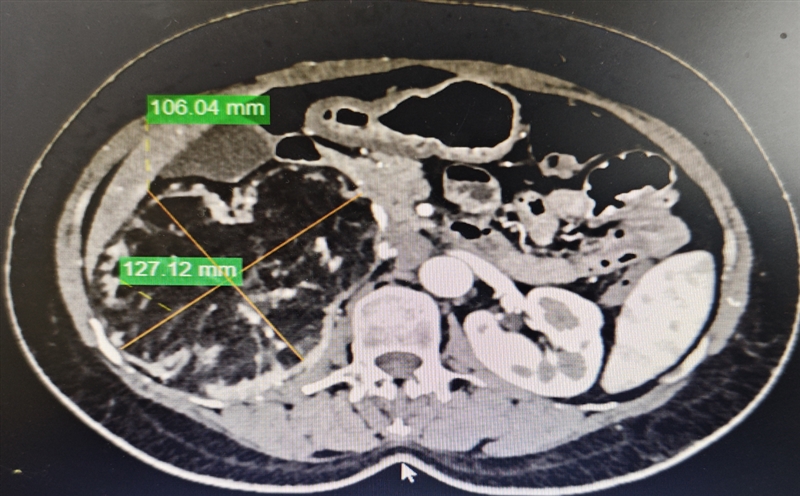

50余岁的患者张女士因强直性脊柱炎在当地医院复查时,意外发现右侧腹部有巨大占位性病变,CT检查显示病灶约成年人大号拳头并拢的大小(12.9cm×9.5cm×13cm)。当地医院无法明确诊断,张女士遂慕名前往重医附二院泌尿外科,找到刘川主任医师就诊。

腹部增强CT提示右肾周围存在巨大肿物。图源 重医附二院

入院完善各项检查后,刘川结合临床经验初步判断为右肾错构瘤。考虑到张女士还合并强直性脊柱炎、高血压等基础疾病,手术难度和风险大幅增加,刘川医疗团队为其制定了个性化的腹腔镜微创手术方案。